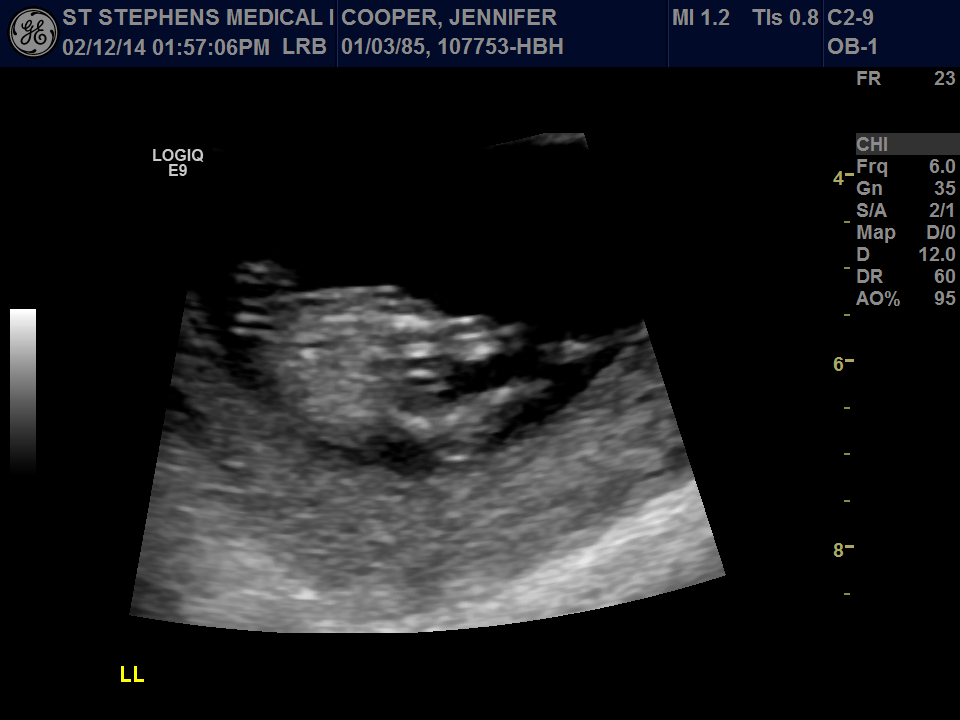

Attachment 22396Had my nuchal translucency ultrasound done yesterday at 12 weeks 4 days, images aren't too clear but wondering if anyone has any thoughts as to baby's gender?

Have added another picture which is a still from the video, unsure for certain whether it's the nub pictured or not.

Any insight at all would be appreciated.